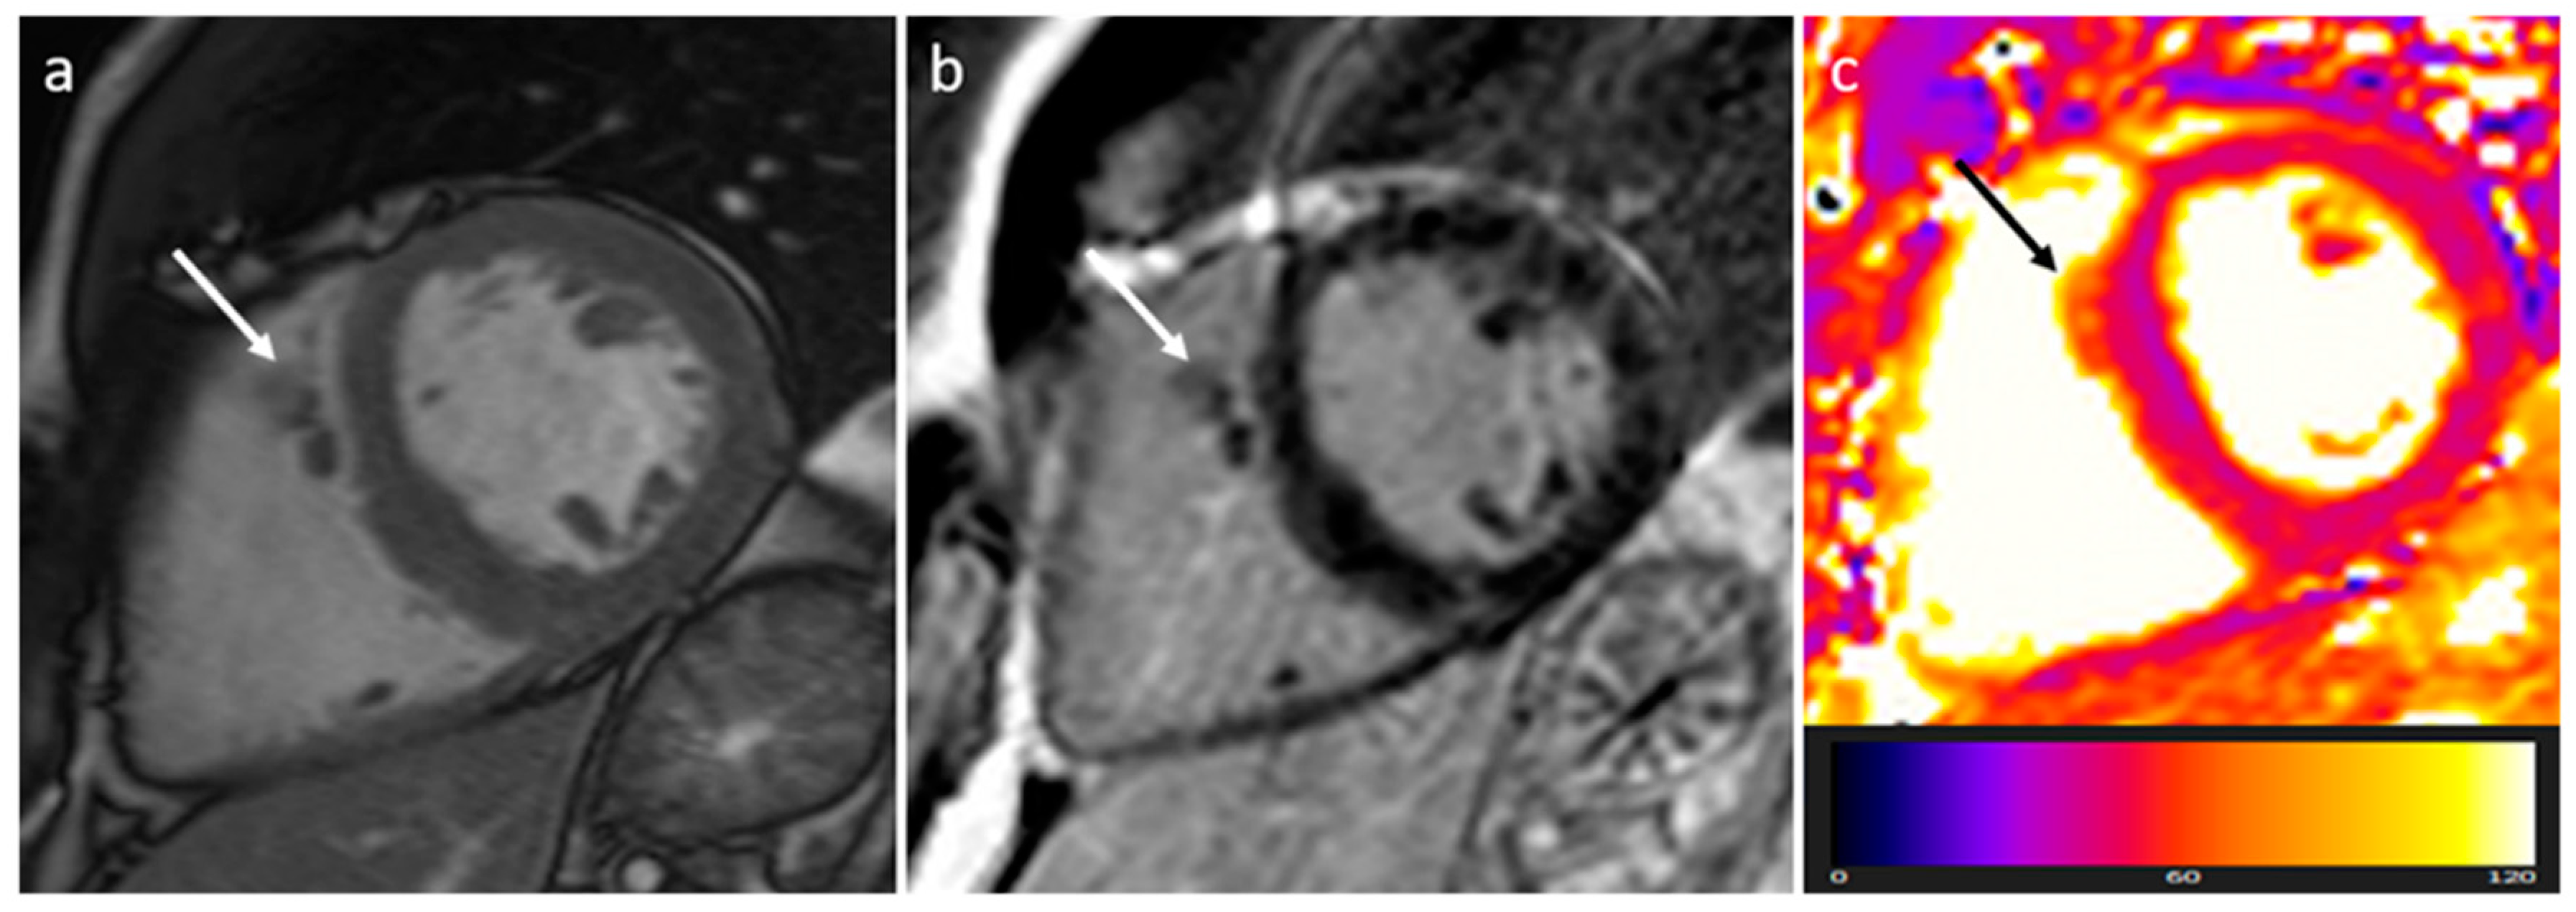

3.8. Sarcoidosis

| Sarcoidosis | Adulthood | Basal septum, AV groove | AV block, LVEF reduction | Basal septal thickening, delayed myocardial enhancement, associated mediastinal/hilar adenopathy | Septal mass lesion | Basal septum thickening, rarely soft tissue infiltration into AV groove encasing the coronary artery | LGE, Active disease (oedema): hyper T2w |